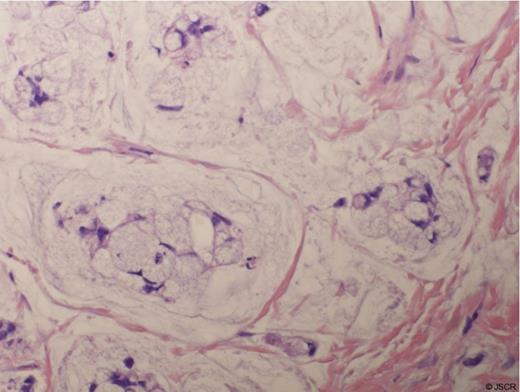

The patient underwent urethral diverticulectomy, during which 2 separate diverticula were noted, one at 5 and one at 7 o’clock. Intra-operative frozen section revealed fibrotic tissue. Final pathology, however, revealed invasive high grade adenocarcinoma involving both diverticula with signet ring cell features and mucin production, see Figure 2.

H&E Stain of the Signet Ring Adenocarcinoma from the Urethral Diverticulum